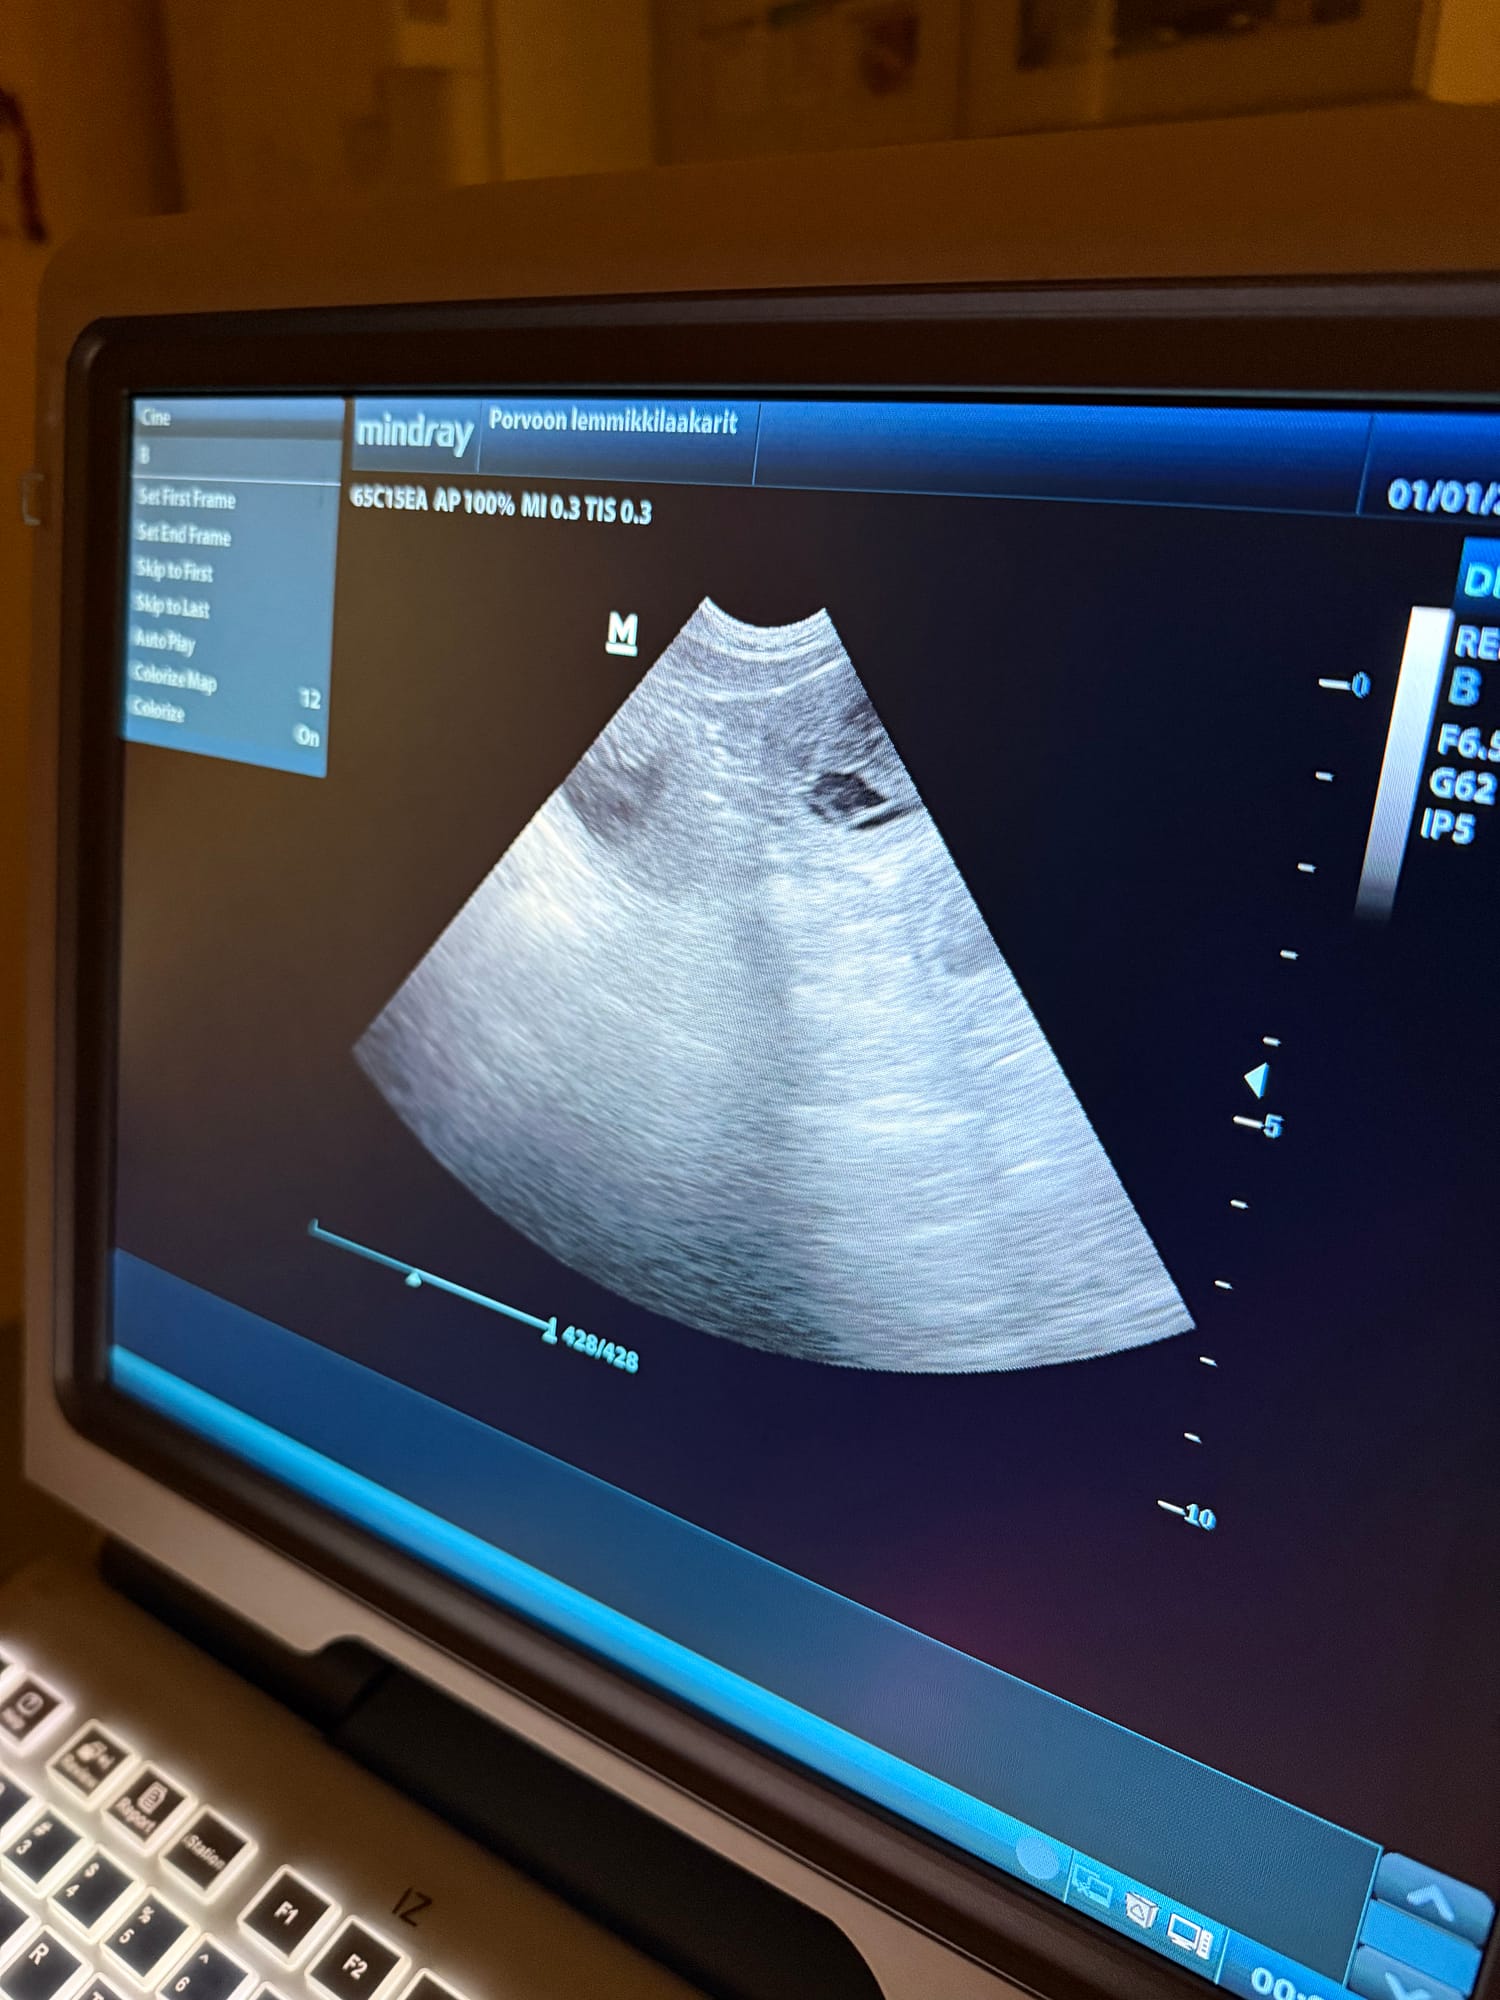

Sera is pregnant!

Today we went for a scan at Lemmikkilääkärit and as I suspected Sera is pregnant! It seems that we are expecting a litter in the larger side but time will tell 🙂